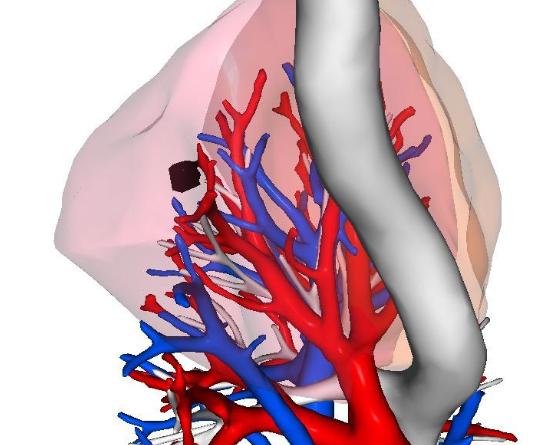

短短6个月,肺结节就从6毫米长到了8毫米?这位患者今年63岁,专程从外地坐飞机来门诊找我。他在体检时查出右上肺有一个实性结节,半年时间就增大了2毫米。 从影像上看,这个结节带有浅分叶,密度也比较高,不少影像科医生都怀疑是早期肺癌,认为发现得很及时。 患者和家属都非常焦虑,态度也很坚决:一定要做手术,他们觉得能这么早发现是“老天帮忙”,必须尽快处理才能安心,再加上看到网上说实性结节很容易出现转移,就更担心了。 虽然结节不大,但位置很深,加上短期内已经出现变化,如果真是肺癌,浸润性和恶性程度可能都不低。如果直接手术,很可能得切掉整个肺叶。 但我心里有些犹豫。因为仔细看影像,结节的边缘其实是光滑的,不能完全排除良性肿瘤的可能。患者已经60多岁,如果直接做肺叶切除,创伤大、恢复慢,对今后的生活质量影响不小。 我认真思索后,建议患者做了三维重建,发现这个结节其实位于右上肺的一个亚段——只需要切除B亚段,范围大约占右肺的5%,比常规的楔形切除范围还小。 这样既能取到组织做病理,也能最大程度保留肺功能。 我们和患者沟通后,决定先做这个亚段切除,术中冰冻病理结果很快出来了:是一个良性软骨瘤。真是非常幸运! 最终,患者只做了一个非常小的切除手术,既明确了诊断,又避免了不必要的肺叶切除。对一位60多岁的老人来说,手术创伤小,恢复也快,基本不影响以后的生活。 这件事也让我再次体会到:作为医生,一定要多站在患者的角度思考,用尽可能小的代价,为他们争取最大的健康获益——这个原则,必须时刻放在心上。[玫瑰][作揖]胸外科乔贵宾医生肺结节[超话]